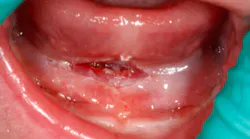

The time spent performing the laser surgery for this frenectomy was less than one minute (figure 5)!

Figure 5: Immediately post-op